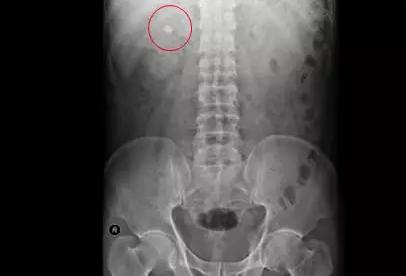

术前KUB

在B超的监视引导下,于右侧腰背部11肋间用PTCD针穿刺右肾含石上盏,拔除针芯后可见尿液流出,然后逐步扩张经皮肾通道并置入工作鞘,然后置入超细经皮肾镜,经输尿管镜可看到,结石大小约1.6X1.2X1.0CM,黄褐色,质地硬,表面粗糙。